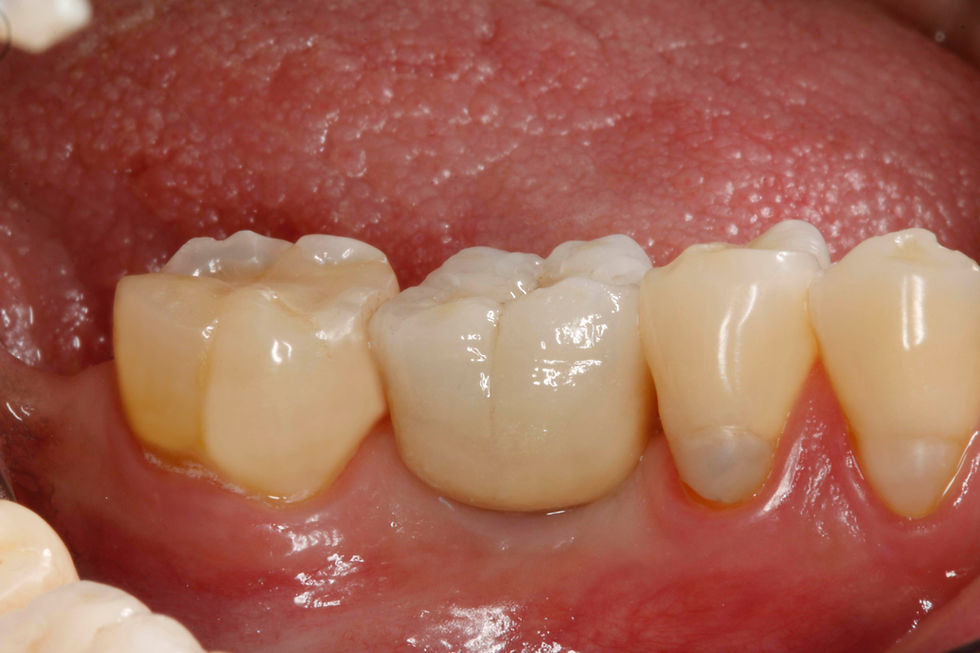

Lateral view of the definitive crown.